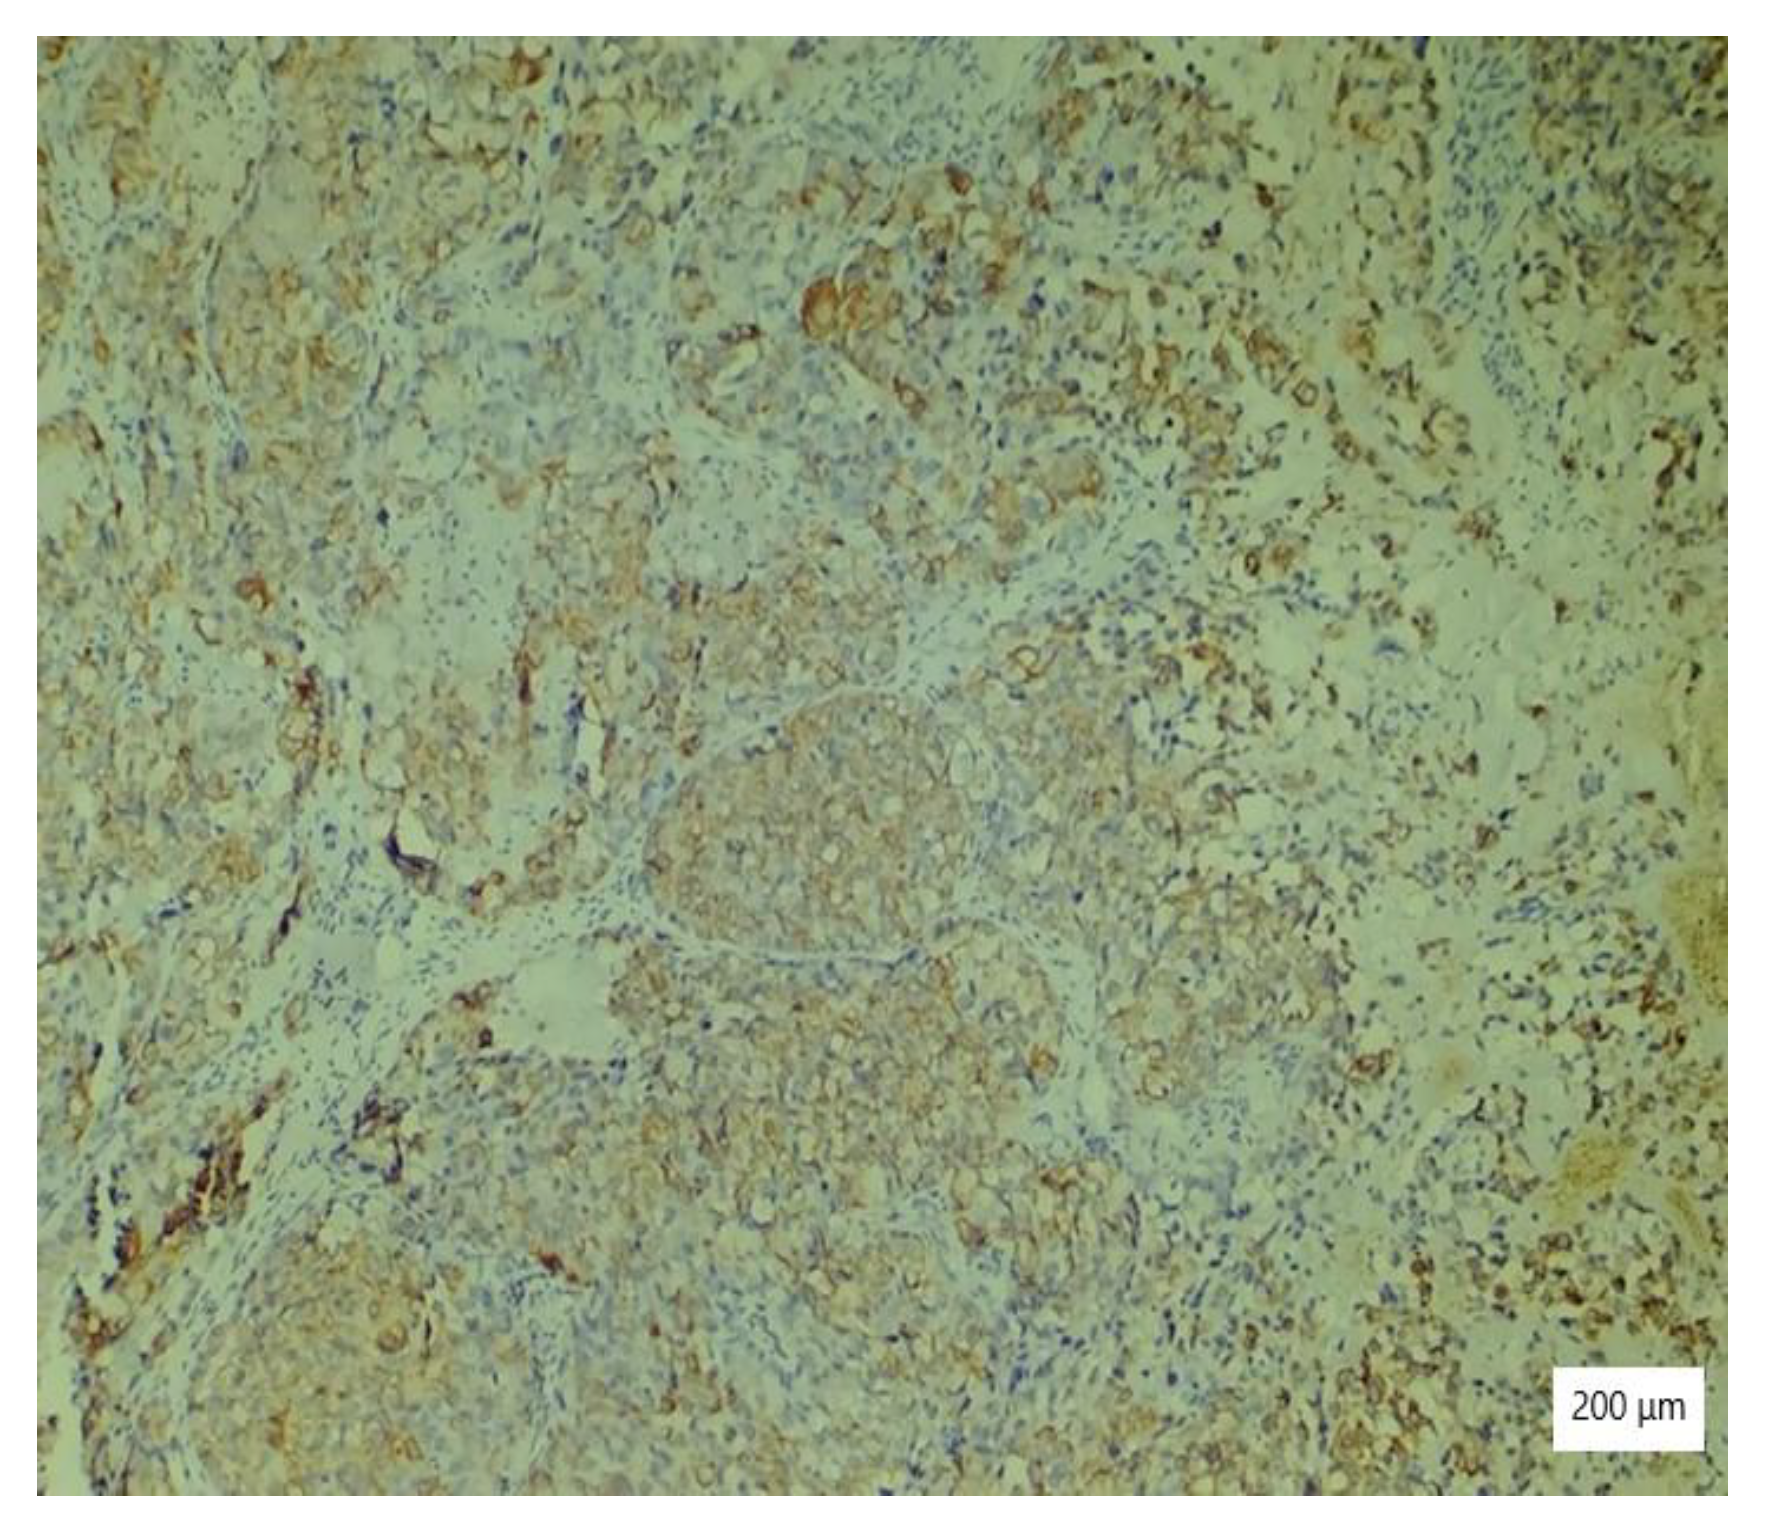

The microscopic analysis of the cervical mass biopsy showed the presence of the following morphological aspects: mixed architecture with solid and tubulocystic patterned areas; mainly composed of nests of cells with clear or eosinophilic cytoplasm (intracytoplasmic glycogen); and prominent hyperchromatic nuclei, some with round nucleoli and high mitotic activity (16/10 HPF) (Figure 2, Figure 3 and Figure 4). Additionally, we noted abundant inflammatory infiltrate that was mainly made up of the lymphocytes and plasmacytes present in the hyalinized stroma, and this was determined to be associated with the area of necrosis. Periodic acid–Schiff staining was strongly positive in the cytoplasm, consistent with glycogen (Figure 5). Immunohistochemical staining showed a diffuse positive reaction for CK AE1/AE3, PAX8, and AMACR; rare cells showed CEA-positive expression; and there was a negative reaction for p63, CD30, OCT4, ER, SALL4, synaptophysin, CD56, and p16, which were focally positive in tumor cells (Figure 6, Figure 7, Figure 8, Figure 9, Figure 10 and Figure 11). The histological diagnosis was HPV-negative clear cell adenocarcinoma of the uterine cervix.

Figure 3. Tubulocystic pattern of tumor cells with clear cytoplasm, inflammatory infiltrate, necrosis, and hemorrhagic areas (HE ×100).